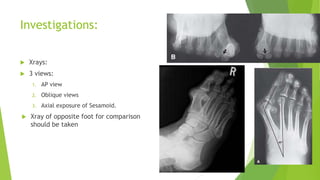

Investigations:

 Xrays:

 3 views:

1. AP view

2. Oblique views

3. Axial exposure of Sesamoid.

 Xray of opposite foot for comparison

should be taken